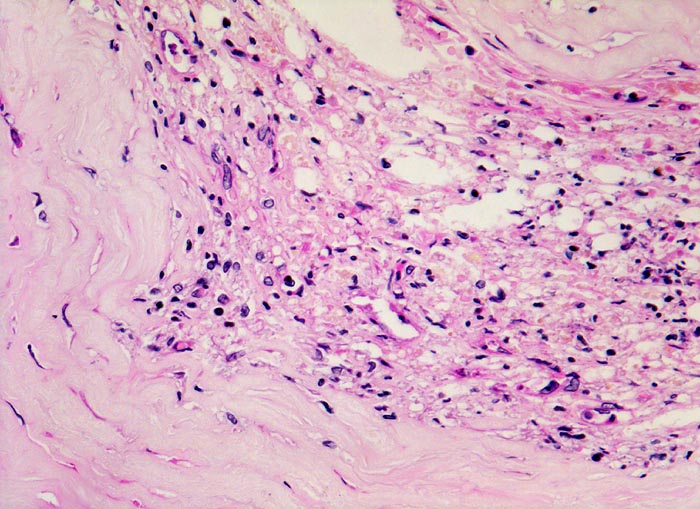

Koronarsklerose: Atherom

Ausschnitt aus der sklerosierten Intima mit Atherom: Herd von Granulationsgewebe mit Kapillaren und lockerem Infiltrat von Lymphozyten, Histiozyten und lipidbeladenen Schaumzellen.

Subakuter transmuraler Myokardinfarkt. In der Anamnese Nikotinabusus und schlecht eingestellte arterielle Hypertonie.

320